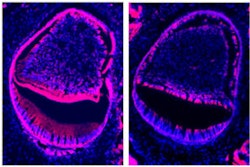

The NF-kB protein, a culprit in inflammatory and immune disorders, plays a major role in both osteoporosis and periodontitis, disrupting the healthy balance of bone destruction and formation. It is this balance that Dr. Wang and his fellow scientists seek to restore, and perhaps even improve upon, by finding new ways to promote net bone accumulation.

"Most studies focus on the part that NF-kB plays in the regulation of osteoclasts. For the past five years, we looked closely at the effect of NF-kB on osteoblasts," Dr. Wang said. "We knew that NF-kB promoted resorption. What we discovered in our in vitro and in vivo studies is that this protein also inhibits new bone formation, giving us a fuller picture of its role in inflammation and immune responses."